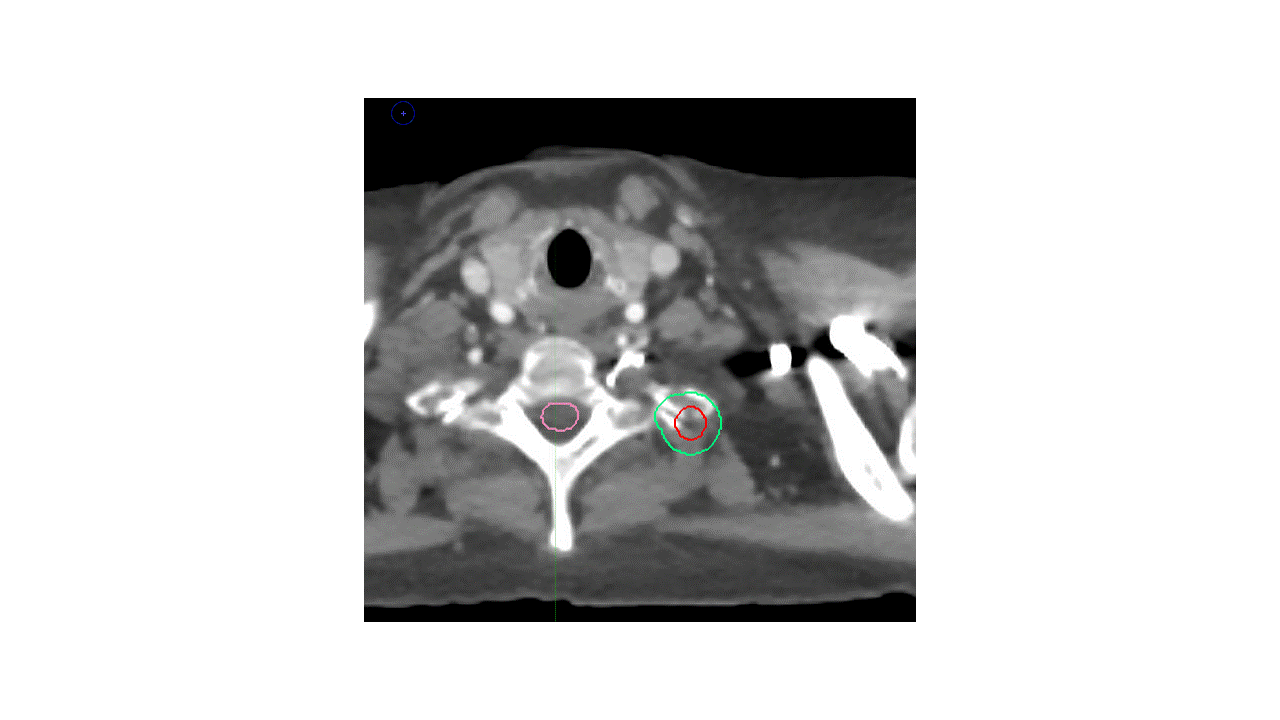

Alternative 1

Alternative 2

Which volumes are the most appropriate?

A. LUL primary tumor with margin, no LN and limited vertebral body inclusion

B. LUL primary tumor + hilar LN, with inclusion of entire vertebral body and left-sided pedicle/process/lamina

C. LUL primary tumor and limited vertebral body inclusion + hilar/mediastinal lymphadenopathy

Answer: B

There are several potential approaches to this case. Given that the mass extends into the vertebral body and the T2 neural foramen, with unclear borders, the International Spine Radiosurgery Consortium consensus guidelines were utilized, with inclusion of the ipsilateral neural foramen and vertebral body substructures. Choices A and C are too limited with respect to vertebral body coverage, and actually appear to miss gross disease. A thin-slice MRI scan was used for treatment planning and a spinal cord PRV was utilized to ensure appropriate coverage with adequate sparing of the spinal cord.

The second major question is whether to cover the left hilum and the mediastinum. Given that the EBUS was negative, it would be reasonable to omit the entire mediastinum. However, in this case, the decision was made to cover the ipsilateral hilum given the strong avidity in the left hilum and the proximity of the mass to the left hilum, this region was covered as well.